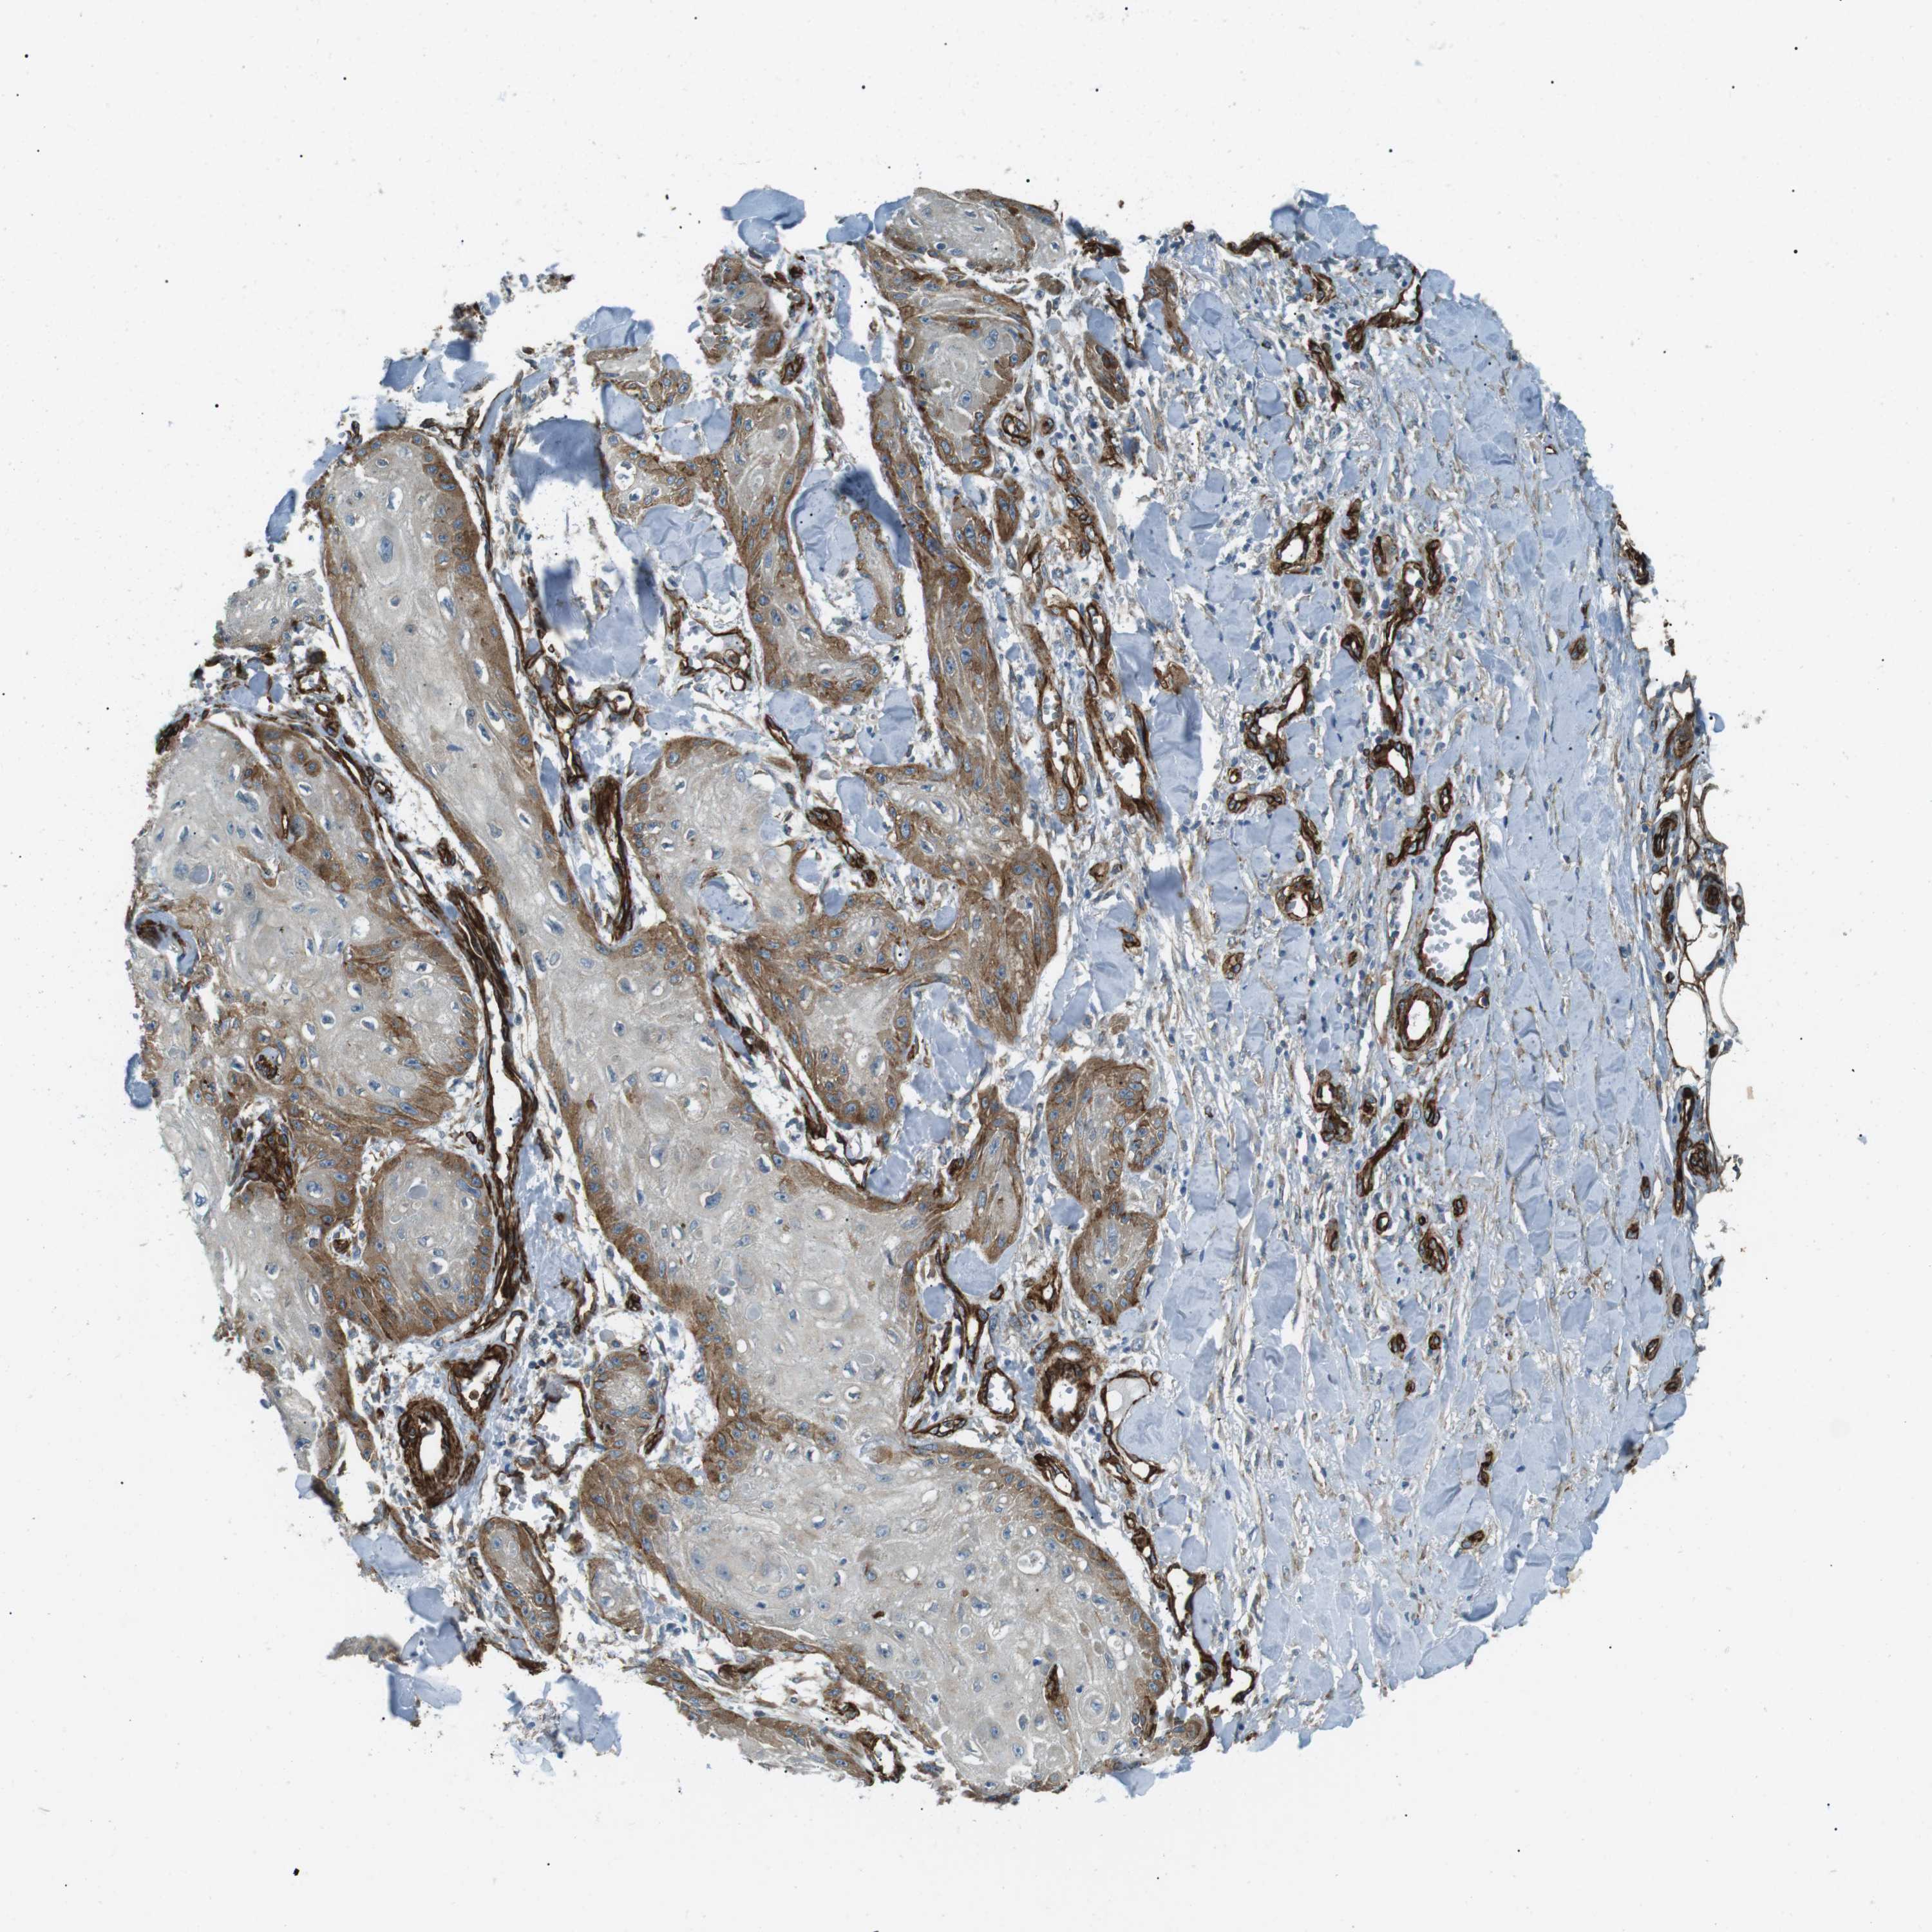

SKIN CANCER - Protein expressioni

A mouse-over function shows sample information and annotation data. Click on an image to view it in a full screen mode. Samples can be filtered based on level of antibody staining by selecting one or several of the following categories: high, medium, low and not detected. The assay and annotation is described here.

Antibody staining in the annotated cell types in the current human tissue is reported as not detected, low, medium, or high, based on conventional immunohistochemistry profiling in selected tissues. This score is based on the combination of the staining intensity and fraction of stained cells.

Each image is clickable and will lead to virtual microscopy that enables deeper exploration of all samples and also displays staining intensity scores, fraction scores and subcellular localization as well as patient and tissue information for each sample.

Antibody HPA015988

Staining

High

Medium

Low

Not detected

Intensity

Strong

Moderate

Weak

Negative

Quantity

>75%

75%-25%

<25%

None

Location

Nuclear

Cytoplasmic/membranous

Cytoplasmic/membranous,nuclear

Squamous cell carcinoma in situ, NOS

Squamous cell carcinoma, NOS

Basal cell carcinoma

Adnexal tumor, benign